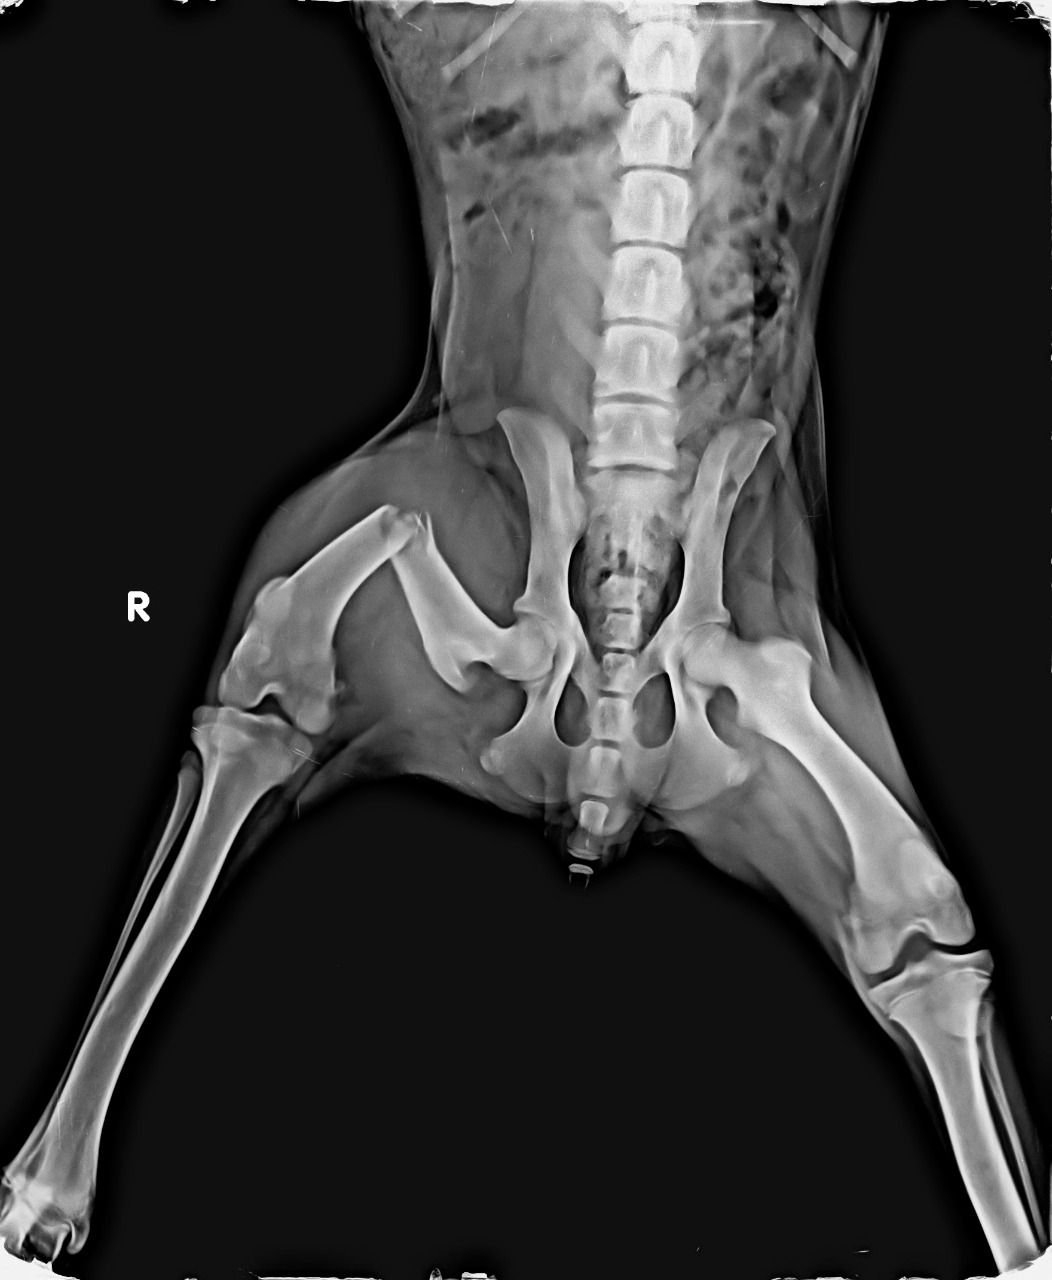

With a aim of “सर्वे भवन्तु सुखिनःI सर्वे सन्तु निरामया:I”, X RAY HOUSE, ANAND started Animal Imaging department for small animals.

We are pioneer of radio-diagnosis in small animals like dog, cat, rabbit, turtle etc. in Gujarat.